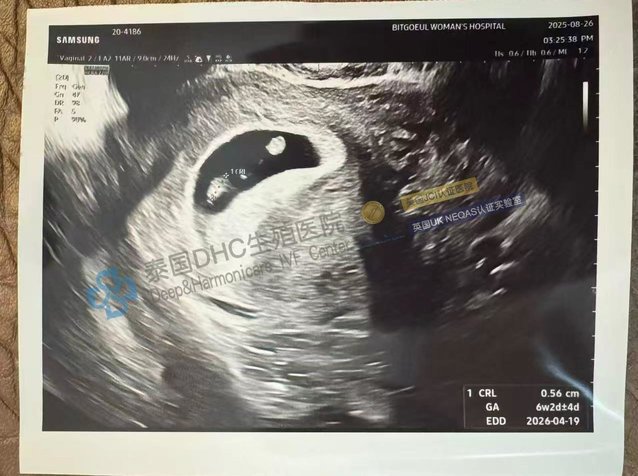

2025-09-01本文將帶您見證泰國DHC生殖醫(yī)院如何將“挑戰(zhàn)”變?yōu)椤捌孥E”。我們將聚焦三個由頂級專家主導(dǎo)的成功案例:一位34歲、AMH僅0.7的客戶如何獲1男1女健康胚胎;一位...

2025-08-28本文將深入剖析泰國DHC生殖醫(yī)院如何為經(jīng)歷復(fù)發(fā)性流產(chǎn)及多重婦科疾病的客戶,實(shí)現(xiàn)從“苦盡甘來”到“聽見花開”的全過程。我們將聚焦一個終極挑戰(zhàn)案例的成功,并分享查雅...

2025-08-27本文將帶您體驗(yàn)DHC的全周期好孕服務(wù)。我們將分享三個環(huán)環(huán)相扣的真實(shí)故事:一位41歲印尼客戶如何在試管前通過多維度養(yǎng)卵方案,將6顆基礎(chǔ)卵泡成功增值至11顆凍卵;一...

2025-08-26本文將帶您走進(jìn)泰國DHC生殖醫(yī)院的“奇跡制造工坊”——我們的胚胎實(shí)驗(yàn)室。我們將聚焦三個震撼人心的案例:一位AMH僅0.5的卵巢早衰客戶,如何實(shí)現(xiàn)100%的養(yǎng)囊奇...

2025-08-25本文將帶您深入了解DHC如何將“奇跡”變?yōu)楝F(xiàn)實(shí)。我們將聚焦三個不同維度的成功故事:一位41歲高齡客戶如何實(shí)現(xiàn)取卵4、養(yǎng)囊4的“零損耗”通關(guān);DHC如何通過精子調(diào)...

2025-08-22本文將帶您了解泰國DHC生殖醫(yī)院如何助力客戶實(shí)現(xiàn)前瞻性的人生規(guī)劃。我們將分享三個代表性故事:一位26歲客戶如何成功冷凍17顆優(yōu)質(zhì)卵子,為未來上好“生育保險”;一...

2025-08-21本文將帶您領(lǐng)略泰國DHC生殖醫(yī)院如何將“挑戰(zhàn)”變?yōu)椤柏S收”。我們將聚焦三個振奮人心的案例:一位37歲多囊客戶如何豪取12枚健康胚胎,實(shí)現(xiàn)“胚胎大滿貫”;一位41...